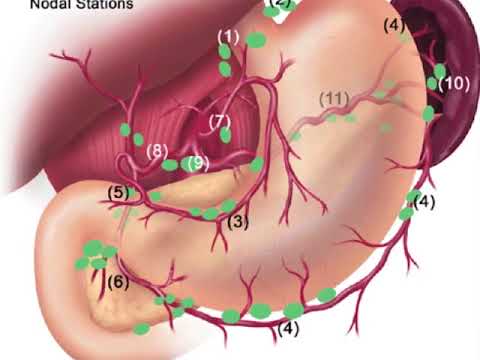

Jaipur Saturday Session 6 Lymph Node

#178 Robotic Lateral Lymph Node Dissection Dr. Ankit Sharma, Dr. Avanish Saklani

A typical Locations of Sentinel Lymph Nodes in Endometrial Cancer